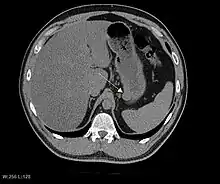

CT scanning is often undertaken (see the radiology section).

The purpose of radiologic imaging is to locate the lesion, evaluate for signs of invasion and detect metastasis. Features of GIST vary depending on tumor size and organ of origin. The diameter can range from a few millimeters to more than 30 cm. Larger tumors usually cause symptoms in contrast to those found incidentally which tend to be smaller and have better prognosis.[5][14] Large tumors tend to exhibit malignant behavior but small GISTs may also demonstrate clinically aggressive behavior.[15]

Barium fluoroscopic examinations and CT are commonly used to evaluate the patient with abdominal complaints. Barium swallow images show abnormalities in 80% of GIST cases.[15] However, some GISTs may be located entirely outside the lumen of the bowel and will not be appreciated with a barium swallow. Even in cases when the barium swallow is abnormal, an MRI or CT scan must follow since it is impossible to evaluate abdominal cavities and other abdominal organs with a barium swallow alone. In a CT scan, abnormalities may be seen in 87% of patients and it should be made with both oral and intravenous contrast.[15] Among imaging studies, MRI has the best tissue contrast, which aids in the identification of masses within the GI tract (intramural masses). Intravenous contrast material is needed to evaluate lesion vascularity.

Preferred imaging modalities in the evaluation of GISTs are CT and MRI,[17]: 20–21 and, in selected situations, endoscopic ultrasound. CT advantages include its ability to demonstrate evidence of nearby organ invasion, ascites, and metastases. The ability of an MRI to produce images in multiple planes is helpful in determining the bowel as the organ of origin (which is difficult when the tumor is very large), facilitating diagnosis.

As the tumor grows it may project outside the bowel (exophytic growth) and/or inside the bowel (intraluminal growth), but they most commonly grow exophytically such that the bulk of the tumor projects into the abdominal cavity. If the tumor outstrips its blood supply, it can necrose internally, creating a central fluid-filled cavity with bleeding and cavitations that can eventually ulcerate and communicate into the lumen of the bowel. In that case, barium swallow may show an air, air-fluid levels or oral contrast media accumulation within these areas.[15][18] Mucosal ulcerations may also be present. In contrast-enhanced CT images, large GISTs appear as heterogeneous masses due to areas of living tumor cells surrounding bleeding, necrosis or cysts, which is radiographically seen as a peripheral enhancement pattern with a low attenuation center.[14] In MRI studies, the degree of necrosis and bleeding affects the signal intensity pattern. Areas of bleeding within the tumor will vary its signal intensity depending on how long ago the bleeding occurred. The solid portions of the tumor are typically low signal intensity on T1-weighted images, are high signal intensity on T2-weighted images and enhanced after administration of gadolinium. Signal-intensity voids are present if there is gas within areas of necrotic tumor.[16][19][20]

Features of malignancy

Malignancy is characterized by local invasion and metastases, usually to the liver, omentum and peritoneum. However, cases of metastases to bone, pleura, lungs and retroperitoneum have been seen. In distinction to gastric adenocarcinoma or gastric/small bowel lymphoma, malignant lymphadenopathy (swollen lymph nodes) is uncommon (<10%) and thus imaging usually shows absence of lymph node enlargement.[14] If metastases are not present, other radiologic features suggesting malignancy include: size (>5 cm), heterogeneous enhancement after contrast administration, and ulcerations.[5][14][21] Also, overtly malignant behavior (in distinction to malignant potential of lesser degree) is less commonly seen in gastric tumors, with a ratio of behaviorally benign to overtly malignant of 3-5:1.[5] Even if radiographic malignant features are present, these findings may also represent other tumors and definitive diagnosis must be made immunochemically.